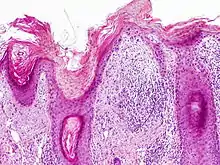

Histopathology

On histologic examination, actinic keratoses usually show a collection of atypical keratinocytes with hyperpigmented or pleomorphic nuclei, extending to the basal layer of the epidermis. A "flag sign" is often described, referring to alternating areas of orthokeratosis and parakeratosis. Epidermal thickening and surrounding areas of sun-damaged skin are often seen.[40] The normal ordered maturation of the keratinocytes is disordered to varying degrees: there may be widening of the intracellular spaces, cytologic atypia such as abnormally large nuclei, and a mild chronic inflammatory infiltrate.[41]

Specific findings depend on the variant and particular lesion characteristics. The seven major histopathologic variants are all characterized by atypical keratinocytic proliferation beginning in the basal layer and confined to the epidermis; they include:[40]